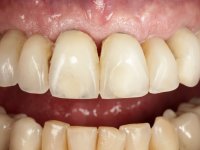

Paciente do sexo masculino, com 64 anos de idade e não fumador. Apresentava uma prótese combinada superior composta por uma ponte metalo-cerâmica fixa de 6 elementos (1.3,1.2,1.1,2.1,2.2, e 2.3) e uma prótese esquelética superior também com 6 elementos. No maxilar inferior apresentava duas pontes metalo-cerâmicas, uma de 3 elementos no 4º quadrante e outra de 2 elementos no 3º quadrante. A adaptação das pontes estava comprometida e esteticamente não satisfaziam o paciente. A higiene oral não era satisfatória.

Foi proposto ao paciente fazer uma reabilitação total superior sobre implantes com colocação de uma prótese provisória aparafusada em carga imediata. Após osteointegração seria colocada uma prótese fixa metalo-cerâmica, se possível, com fixação aparafusada. No maxilar inferior foi proposta a colocação de 3 implantes no 4º quadrante para suportar uma ponte metalo-cerâmica de 3 elementos.